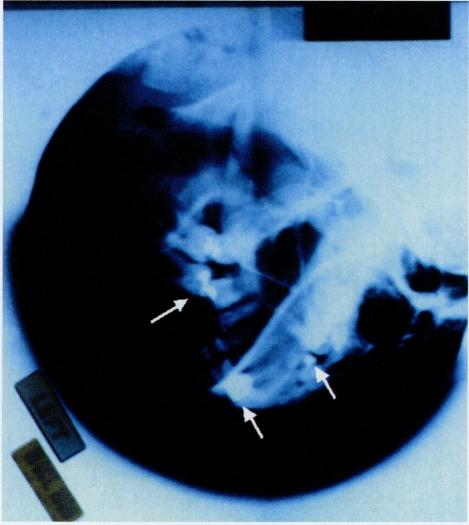

Our objective is to present a case of symptomatic lead toxicity (plumbism) with abdominal colic and hemolytic anemia following a gunshot wound. It is a retrospective case report and the setting is in a teaching hospital in south central Los Angeles. The case report is that of a patient who presented with abdominal pain, generalized weakness, and hypertension following multiple gunshot wounds, 15 years previously. Other causes of abdominal pain and weakness--such as diabetes mellitus, alcohol abuse, pancreatitis, and substance abuse--were ruled out. Interventions included treatment with the newer oral chelating agent, Succimer (2, 3-dimercaptosuccinic acid), and subsequent surgery. The main outcome was the initial reduction in blood lead levels with improvement of symptoms. Because of a recurrent rise in the blood lead levels, the patient was again treated with Succimer and underwent surgery to remove two bullet fragments from the face. We conclude that lead toxicity should be ruled out in patients presenting with abdominal cramps and a history of a gunshot wound. Prompt therapy--including environmental intervention and chelation therapy--is mandatory, and surgical intervention may be necessary.

我们的目的是报告一例枪伤后出现腹部绞痛和溶血性贫血的症状性铅中毒(铅毒症)病例。这是一篇回顾性病例报告,背景是洛杉矶中南部的一家教学医院。该病例报告的患者15年前因多处枪伤出现腹痛、全身无力和高血压。腹痛和无力的其他原因,如糖尿病、酗酒、胰腺炎和药物滥用,均被排除。干预措施包括使用新型口服螯合剂二巯基丁二酸进行治疗,以及随后的手术。主要结果是血铅水平初步降低,症状改善。由于血铅水平反复升高,患者再次接受二巯基丁二酸治疗,并接受手术从面部取出两枚子弹碎片。我们得出结论,对于有腹部绞痛和枪伤史的患者,应排除铅中毒。必须进行及时治疗,包括环境干预和螯合疗法,可能还需要手术干预。